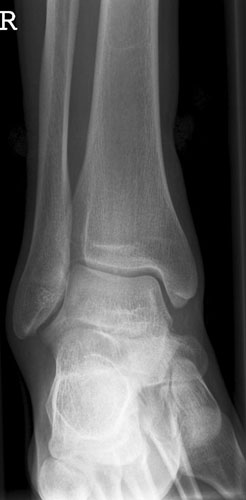

OSG a.p.

OSGapkeineRotation.jpg

Fehler

Leichte Außenrotation des Fußes. Die laterale Kante der distalen Tibia springt besonders markant vor und verdeckt teilweise den Schaft der Fibula.

Abhilfe

Fuß weiter nach innen drehen lassen, bis beide Malleolen auf einer Höhe parallel zum Film stehen.